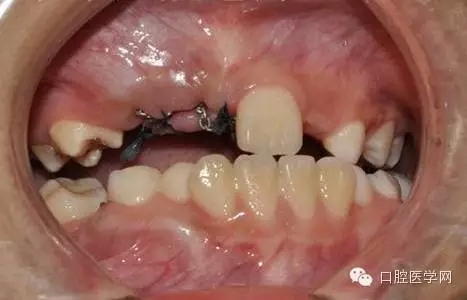

去除部分礙事牙囊,充分暴漏牙冠便于粘結(jié)正畸附件,并用大量腎上腺素壓迫止血。

27.webp.jpg

酸蝕后

28.webp.jpg

光固化型正畸粘結(jié)劑粘結(jié)鏈?zhǔn)綘恳b置

29.webp.jpg

鏈狀正畸牽引裝置粘固后的口內(nèi)情況

30.webp.jpg